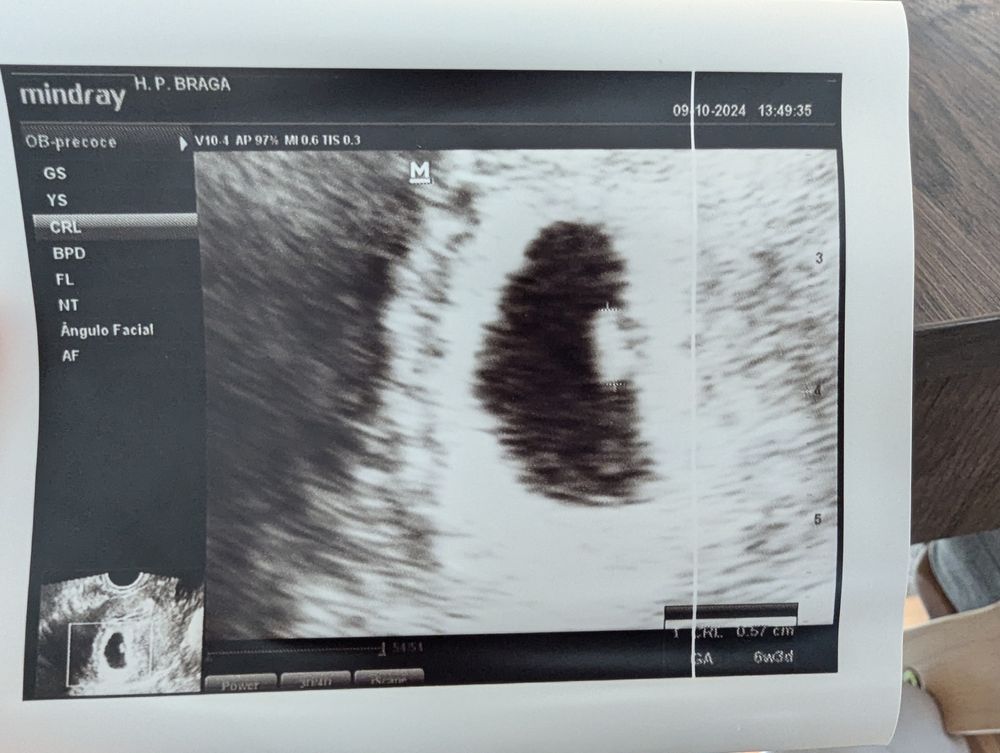

На УЗИ нашли плодное яичко, эмбрион 0.57 см и желточный мешочек.

Сердечко трепещет уже ❤️

Такие мы креветочки вот